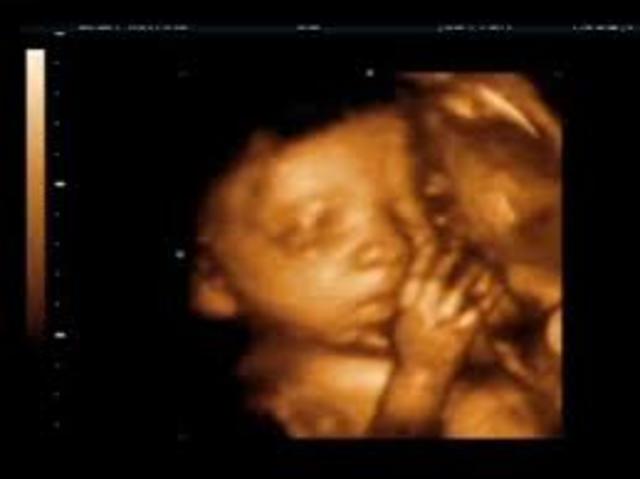

Fetal Development- Ava Kennedy

• 6-7 Months

6-7 Months

Eyes open, fat added under skin, and head out of proportion to the body